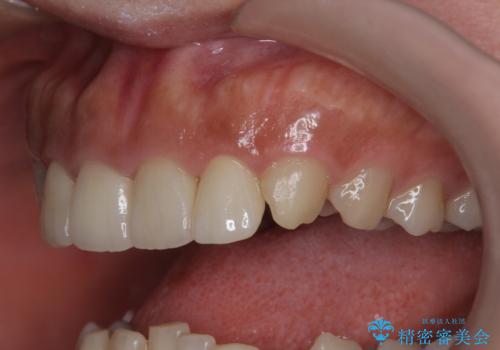

欠けた前歯を綺麗にしたい

- 「欠けてしまった前歯のコンポジットレジン修復をくり返していたが、すぐ外れてしまい困っている。」

、と前歯の欠けの改善を求めて来院されました。

噛み合わせが深く、前歯の突き上げが大きいため欠けの繰り返しを防ぐべくセラミッククラウンによる補綴を行うこととしました。

審美性の改善を達成することができました。